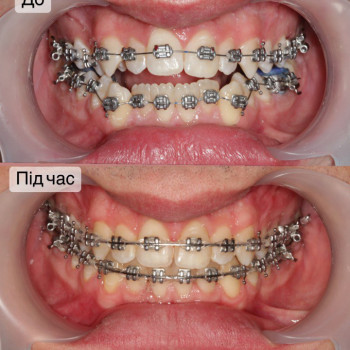

Якщо ти хочеш рівні зуби та красиву посмішку - тобі саме до нас!

Ми зробимо це на високому рівні!

А як саме наважитись на постановку брекетів?

Перший крок - це консультація ортодонта, Ви зможете дізнатись відповіді на запитання які Вас хвилюють. Перед постановкою брекетів усі зубки мають бути здорові, якщо ми бачимо карієс, його потрібно полікувати. Також потрібно зробити рентгенівські знимки для діагностики. За цей час, коли ми готуємо зуби до постановки брекетів, Ви зможете налаштуватись морально, звикнути з думкою що Ваша посмішка засяє новими барвами. На сьогоднішній час носіння брекетів являється престижним!